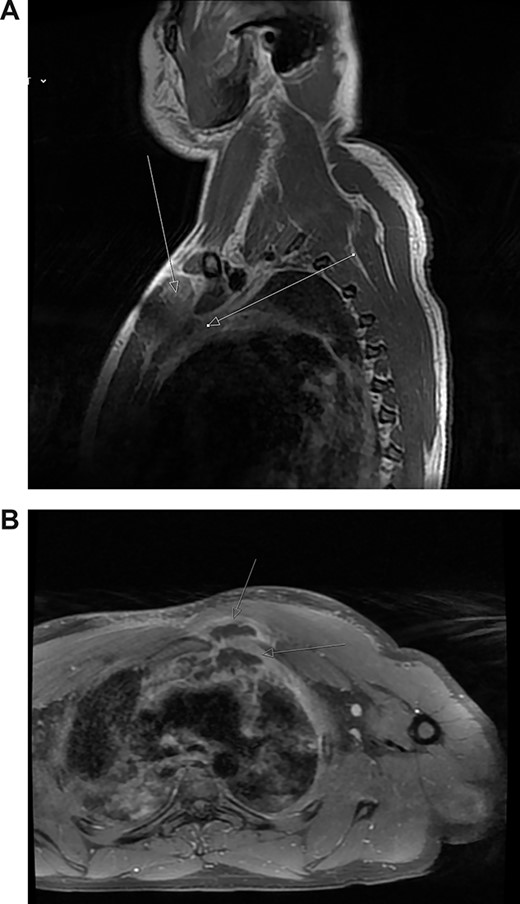

Magnetic resonance imaging (MRI) performed 1 day after admission showed inflammation and oedema at the superior and medial aspect of the left pectoralis muscle suggesting myositis. This inflammation extended to the left second sternocostal joint, the superior and posterior border of the manubrium abutting the anterior margin of the left brachiocephalic vein to indicate mediastinitis (Fig. 2a). No abnormality was seen in the joints, bone or bone marrow.

(A) Post-contrast MRI scan showing areas enhancement around pectoralis major (myositis) with extension into the mediastinum (mediastinitis) (white arrows). (B) New rim-enhancing collections within left pectoralis major muscle. The collection appears to extend posteriorly into the anterosuperior mediastinum (white arrows)